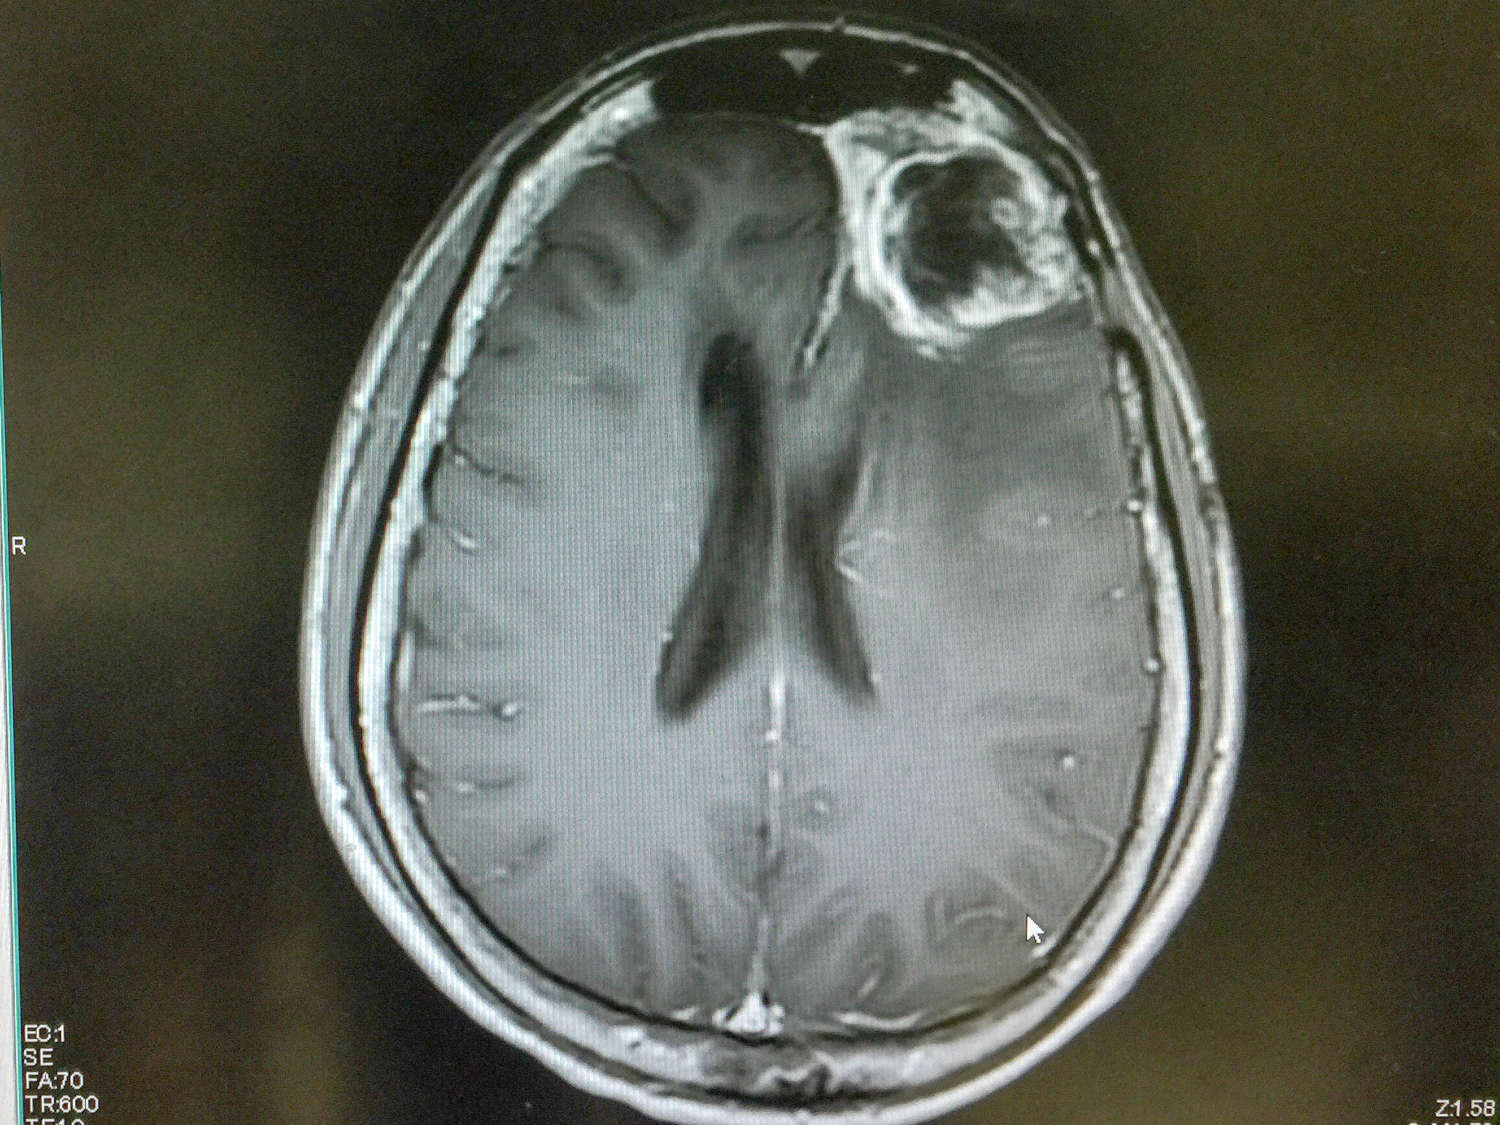

L’esame di elezione per la diagnosi del glioblastoma è la risonanza magnetica con mezzo di contrasto (con un diametro medio del tumore al momento della diagnosi compreso tra 5 e 10 cm), sebbene anche la TAC possa offrire preziose indicazioni.

Shutterstock/O_Akira